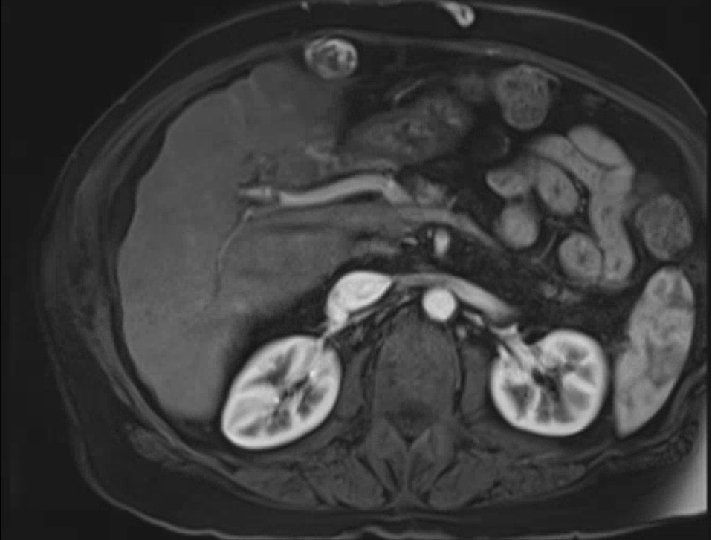

• 74 y. o. male with a large left lobe HCC involving Segment

• 74 y. o. male with a large left lobe HCC involving Segment II, III, and IV also with left portal vein thrombosis. Biopsy confirmed at OSH as moderately differentiated HCC. BCLC stage C tumor. Child-Pugh A with an ECOG PS of 0. Patient presented to MGH for consideration of radioembolization. Patient did not desire chemotherapy due to significant side-effects

Pre-presentation MRI

Pre-SIRT